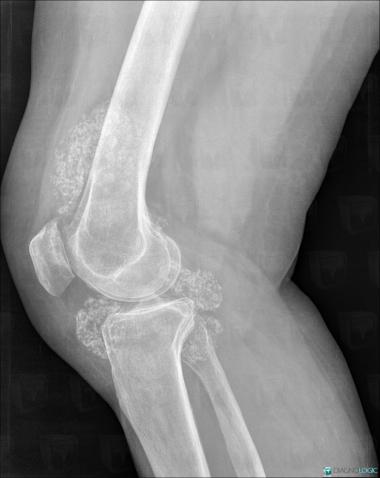

Ostéochondromatose synoviale, Articulations fémoro tibiales / Echancrure, Autres parties molles/nerfs - Genou, Radio

Voici les informations spécifiques à l'image clé ci dessus:

- Diagnostic Ostéochondromatose synoviale, Localisation(s) Articulations fémoro tibiales / Echancrure, comportant les gammes Arthropathie avec nodules des parties molles, Masse des parties molles juxta articulaires, Calcification intra ou périarticulaireAutres parties molles/nerfs - Genou, comportant les gammes Masse des parties molles juxta articulaires, Masse calcifiée des parties molles, Calcifications des parties molles